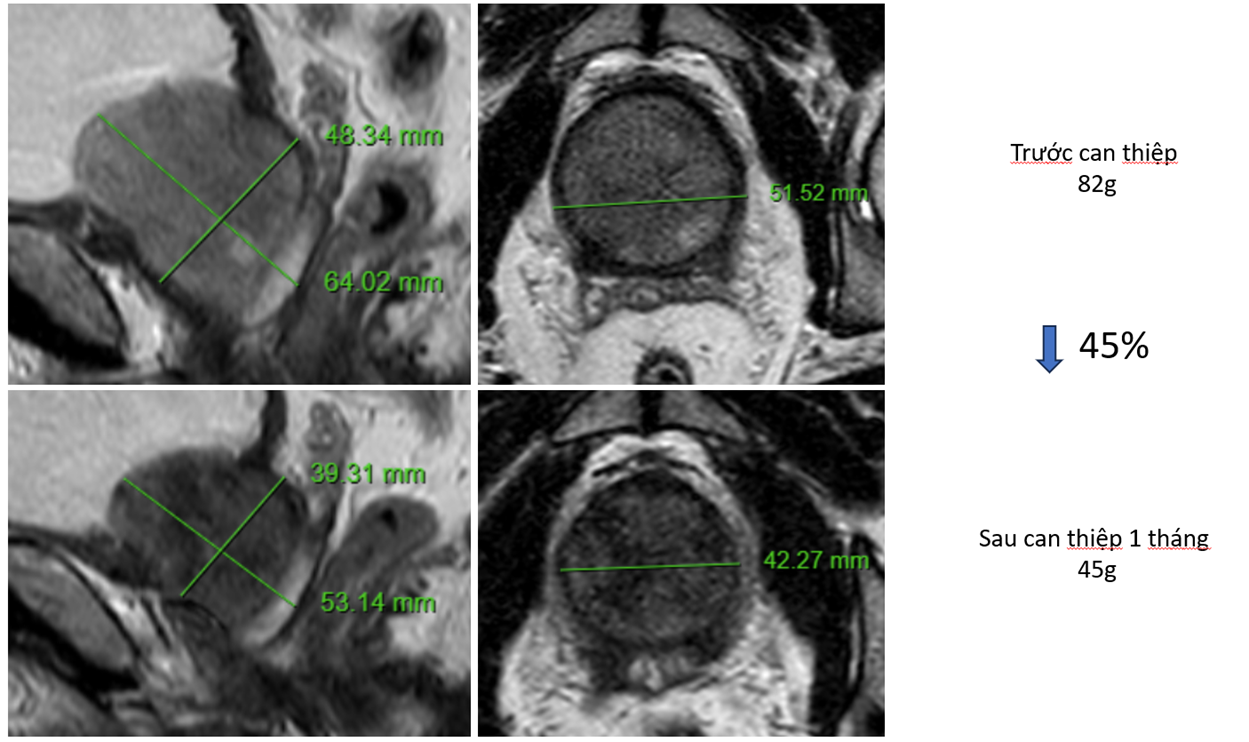

Hình ảnh tuyến tiền liệt giảm 45% thể tích, IPSS từ 26 xuống 6 điểm. QoL từ 4 xuống 1 điểm sau 1 tháng can thiệp